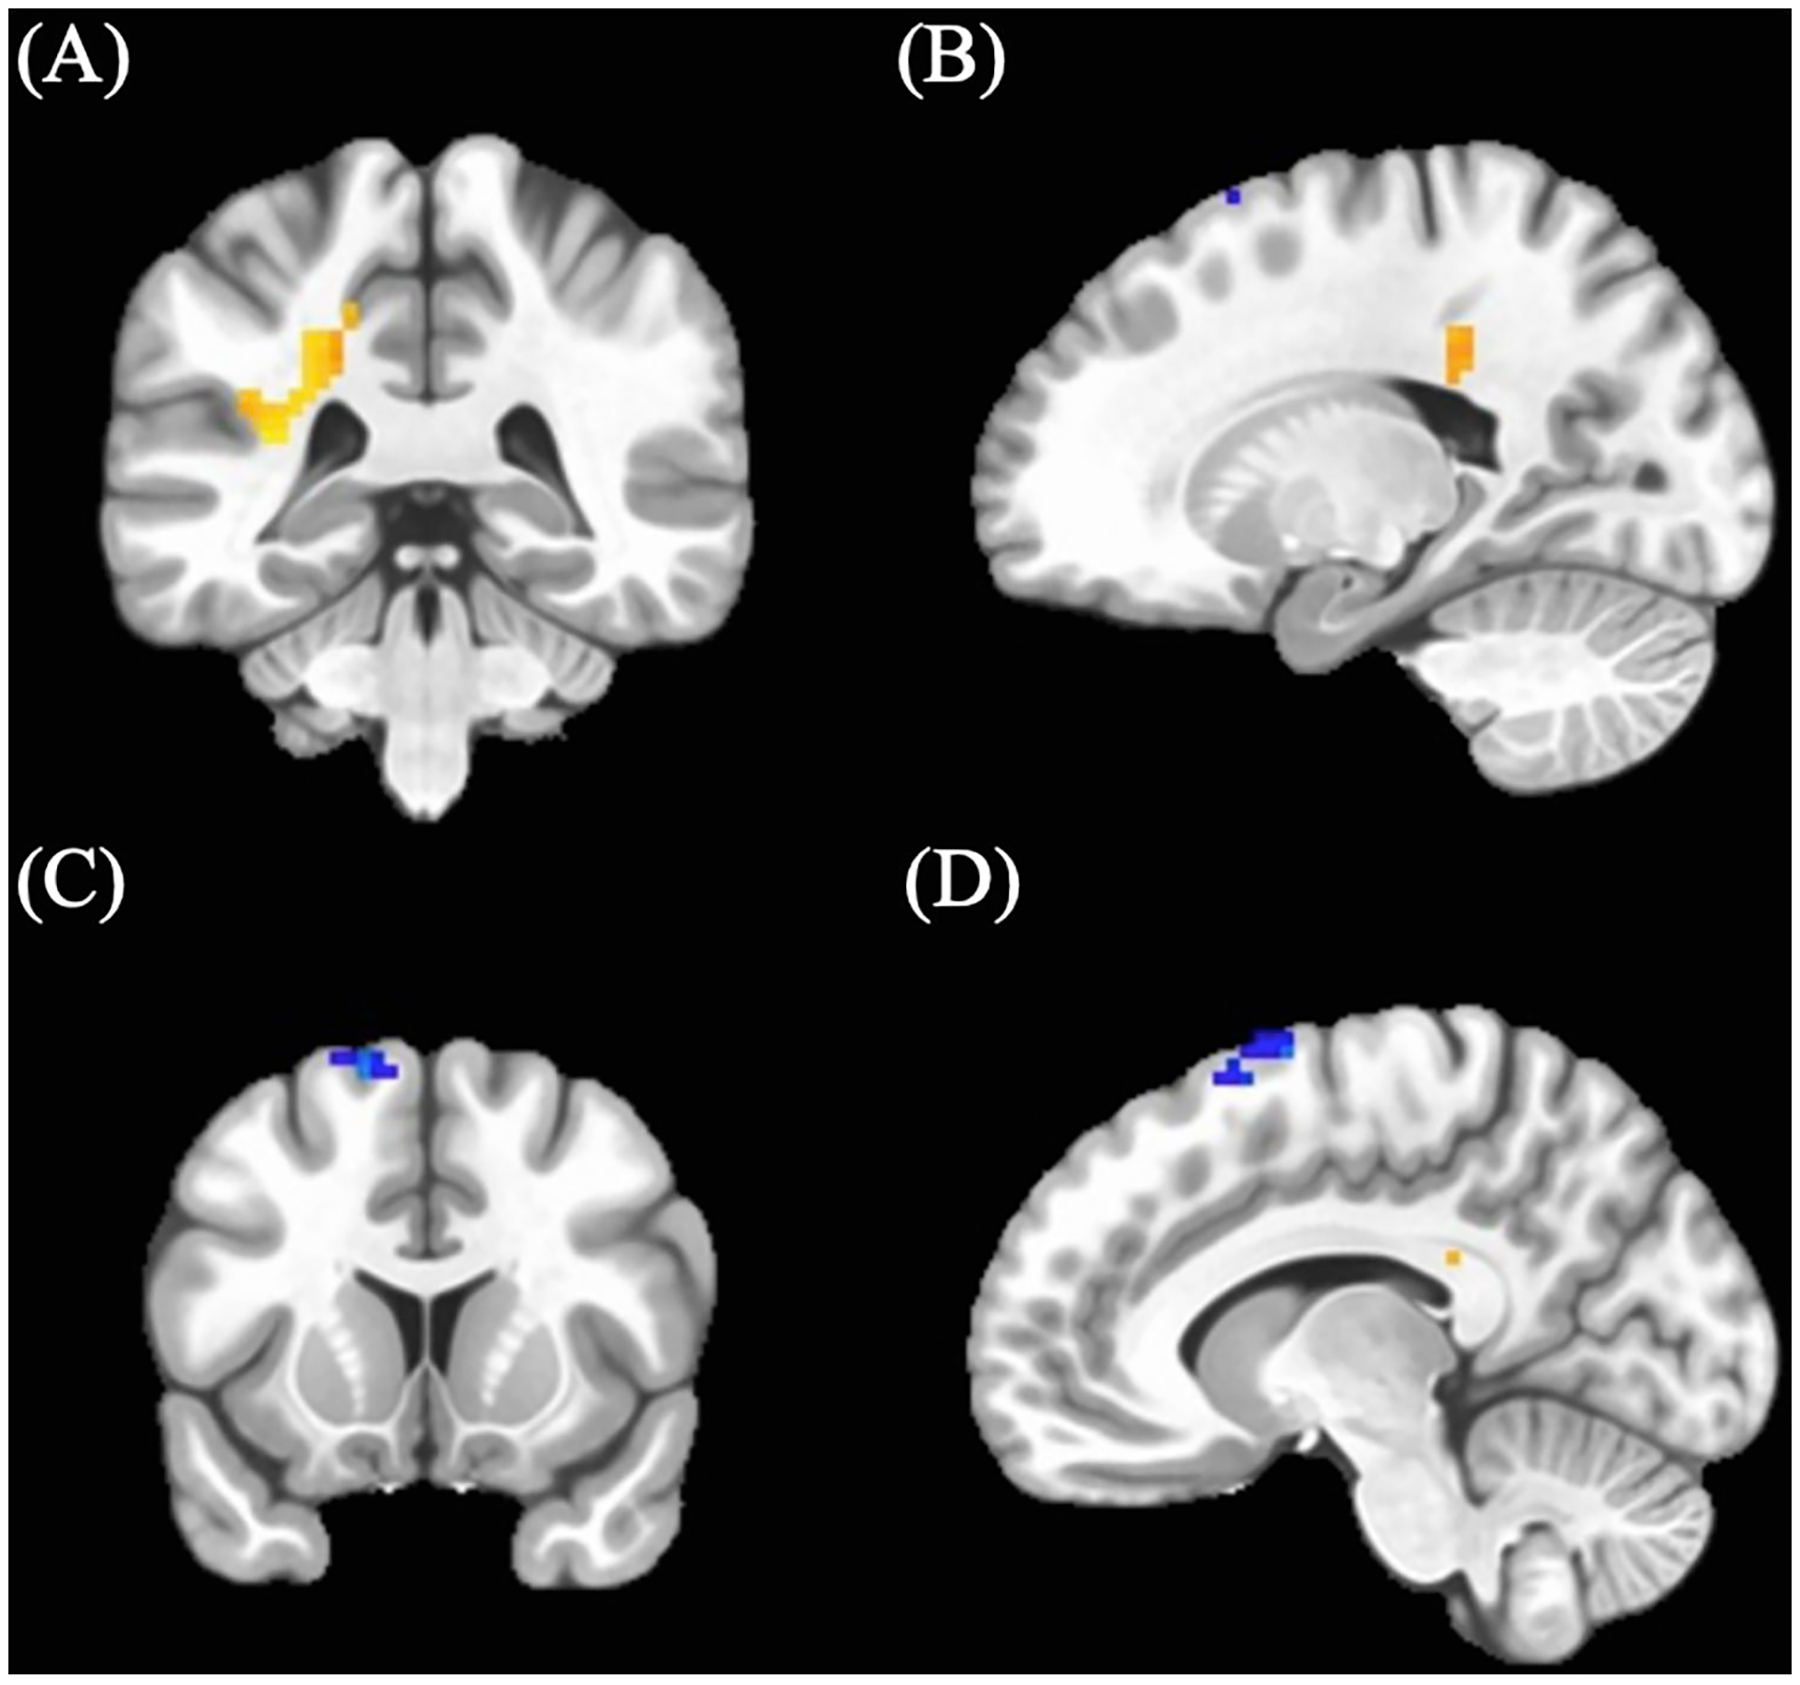

Cannabis-using participants showed a cluster of increased BOLD response (M = 0.05, SD = 0.037) in an area including the left middle cingulum (see Table 3; Figure 1) relative to control participants (M = 0.02, SD = 0.068). In addition, cannabis-using participants displayed a cluster of decreased BOLD activation (M = 0.13, SD = 0.21) in the left supplemental motor area (see Table 3; Figure 1) relative to controls (controls: M = 0.19, SD = 0.31).

TABLE 3: Significant BOLD clusters.

| Cluster # | Voxels | MNI coordinatesa | Annotationsb | Directionality | ||

|---|---|---|---|---|---|---|

| Peak x | Peak y | Peak z | ||||

| Cannabis Findings – Positive > Neutral Go | ||||||

| 1 | 49 | −22.5 | −37.5 | +34.5 | Left Middle Cingulum | Cannabis-using > Control |

| 2 | 26 | −10.5 | +7.5 | +73.5 | Left Supplemental Motor | Cannabis-using < Control |

| Cannabis Findings – Positive > Neutral No-Go | ||||||

| 1 | 18 | −16.5 | +49.5 | +46.5 | Left Superior Frontal | Cannabis-using < Control |

Positive no-go > neutral no-go effects

Cannabis-using participants showed decreased BOLD response (M = −0.25, SD = 0.43) in the left superior frontal region compared to controls in the positive > neutral no-go condition (see Table 3; Figure 2) (controls: M = −0.01, SD = 0.43). (See Table 3).

Cannabis-using adolescents and young adults displayed increased activation in the left middle cingulum and ventral striatum, and decreased activation in left supplemental motor area relative to control participants while freely responding to positive faces (i.e., happy Go). The cluster identified as the left middle cingulum is positioned primarily within anterior cingulum white matter tract, which corresponds with increased cingulate activity when viewing positive faces (ref. 52), though, also shares proximity with the inferior parietal region. Notably, the inferior parietal region has been implicated in cannabis fMRI investigations, demonstrating increased BOLD responding in Go conditions among adolescents (ref. 61), decreased BOLD responding in positive word conditions in young adults (ref. 83), and aberrant inferior parietal-cerebellar connectivity on a Go/No-go task (ref. 84, ref. 85). As this cluster additionally sits within the anterior cingulum bundle, it is worth discussing the relevance of this primarily white-matter activity finding as well given that white matter exhibits activation and functional BOLD differences are worthy of documentation (i.e., instead of the approach to censor for solely grey matter activation) (ref. 86). It is possible that activation within these white matter may represent broader recruitment of cingulum and surrounding regions for task performance, and their corresponding communicating fibers, however, this should be further investigated using network-based analyses of task-related BOLD data to comprehensively examine gray and white matter contributions to these group differences. Notwithstanding, research has identified impacted cingulum development due to cannabis use across young adults (ref. 87) with reduced structural volumes observed (ref. 88, ref. 89). Notably, the anterior cingulum plays a role in both executive functioning and emotion processing (ref. 90) and has been implicated in Go/No-go task performance within community samples (ref. 91). Follow-up analyses should continue to investigation structural/functional network-related characteristics of cannabis use disorder in adolescence.

Analyses additionally observed increased ventral striatum activity during positive response conditions, which corresponds with hyperactivation seen during the reward outcome trials on the MID task among cannabis-using groups (ref. 30, ref. 45, ref. 46). This may possibly represent shared activation patterns for positive facial stimuli and monetary reward stimuli. Hyperactive regions observed within our cannabis group may be indicative of increased recruitment in order to complete the task similar to their non-using peers (i.e., maintain rule set to initiate motor response to positive faces); alternatively, increased activation in cingulum and ventral striatum regions could demonstrate sensitized responses to reward processing within cannabis-using groups, despite similar behavioral performance and abstinence length. Lastly, decreased left supplemental motor activation observed is consistent with findings specifically on tasks requiring motor response (ref. 92, ref. 93). As all three regions (left middle cingulum, left supplemental motor, and ventral striatum) are rich in CB1 receptors (ref. 94, ref. 95), aberrant activation in these areas may be suggestive of compensatory mechanisms by which cannabis-using participants are more heavily recruiting middle cingulum and ventral striatal regions due to positive nature of task condition, while non-using controls more readily engage supplementary motor areas to respond to positive stimuli.

Decreased left superior frontal and ventral striatum activations were observed in positive response inhibition (i.e., happy No-go) for cannabis-using participants relative to controls. Studies of BOLD activation elicited by inhibitory tasks have shown that cannabis-using groups generally display aberrant BOLD response in frontal regions (ref. 59, ref. 61, ref. 84, ref. 96). In a similar sample, Wallace et al. (ref. 13) found increased activation in left frontal gyrus when examining response inhibition to calm (i.e., neutral) faces. Further, given the mixed findings on BOLD response elicited by positive stimuli (ref. 52, ref. 56, ref. 57), we demonstrate a unique pattern of left superior frontal activation in inhibitory trials with added component of inhibition to positive stimuli. While we do see in non-using teens that more frontal activation is recruited for successful inhibitory response to positive faces (ref. 21, ref. 23), it is hypothesized that cannabis-using participants may not be actively recruiting frontal regions; further evidenced by connectivity studies of reward paradigms, where frontal connectivity network differences are observed even following a period of monitored abstinence (ref. 40, ref. 41). Hypoactivation was observed in positive inhibition trials which additionally aligns with previous MID studies of reward anticipation (ref. 30, ref. 44–ref. 46), however, as this task did not involve “anticipation” per se, these findings may instead represent discrepant BOLD responses elicited by positive inhibition. Findings could be attributed to more effortful inhibition of the ventral striatum when cannabis-using individuals are asked to inhibit response to positive (i.e., rewarding) faces in order to complete the task (relative to the non-using literature 97). Overall, the positive inhibition findings may represent that when cognitive control components are added it could disrupt typical reward processing. Future studies with tasks engaging both inhibition and reward processing are needed as these could present more ecologically valid day-to-day interactions with rewarding stimuli.